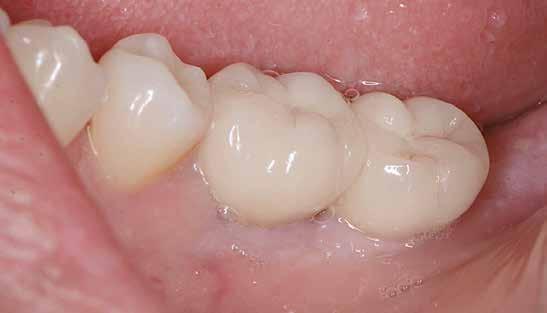

16. ábra: Klinikai kép az implantátumok körüli lágyszövetről a végleges pótlásátadás után. – 17. ábra: Klinikai kép az implantátumok körüli lágyszövetről egy évvel az átadást követően. – 18. ábra: Klinikai kép az implantátumok körüli lágyszövetről két évvel az átadást követően. – 19. ábra: Klinikai kép az implantátumok körüli lágyszövetről öt évvel az átadást követően.

ságát egy ISO #15-ös endodonciai fájllal mértük 2 mm-re a marginális ínyszéltől meziálisan, disztálisan, illetve az implantátum tengelyében (mint referenciapont). A keratinizált íny szélességét parodontológiai szondával regisztráltuk a kiindulás és a kontrollvizsgálatok alatt. A méréseket elvégeztük a műtét előtt, közvetlenül utána, 4 héttel később, majd egy és két év elteltével. A klinikai paramétereket (keratinizált íny szélessége, lágyszövet volumen és recessziófedés) regisztráltunk a kiinduláskor és az utánkövetés időpontjai alatt. Kiinduláskor a feszes íny szélessége minimális volt (1 mm). A keratinizált ínyszélesség terén négy hétnél 2 mm-t sikerült nyerni, egy évnél 3 mm-t és öt év alatt 5 mm-t. A recessziót 100%-osan sikerült fedni 4 hét után, és ez nem változott sem egy év, sem öt év után.